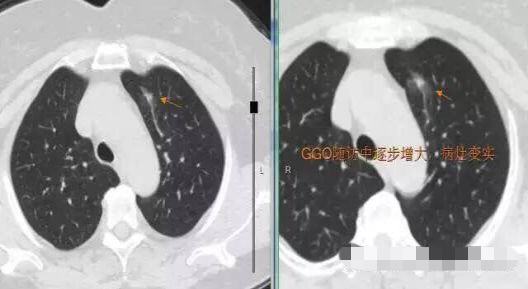

2013年发现, 每年随访,随访至2016年,病灶逐步增大,2013年5毫米大小,2016年11毫米,3年生长6毫米,平均每年2毫米